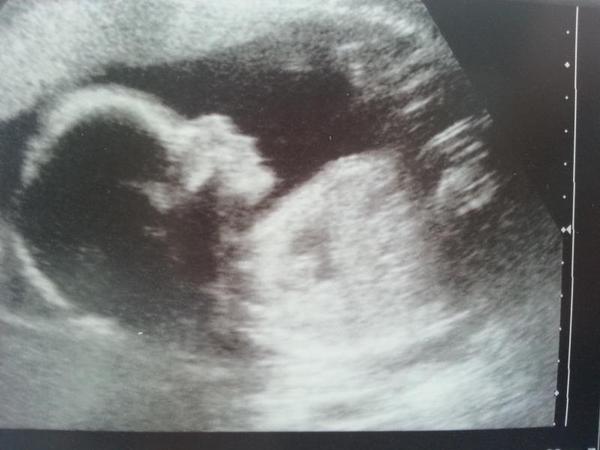

In other pointlessness, does anyone want to guess gender of bub? I don't know if I asked before and can't find my scan post on here. Haha. I was all excited to get a profile shot of baby to get gender guesses then completely forgot to ask!

Just popping in quick to say scan done and everything fine Smile. We're having a girl Grin. The sonographer had to wake her up as she was too busy sleeping and sucking her thumb!!! So cute.